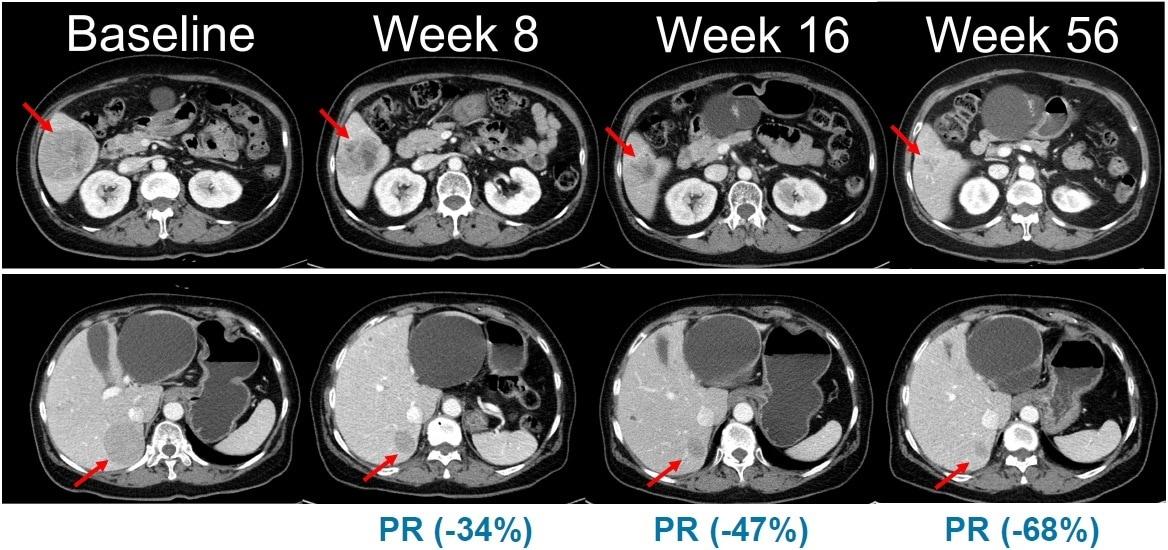

이번 임상 2상은 총 45명의 환자를 대상으로 표적 항암신약 벨바라페닙과 MEK 억제제인 '코비메티닙'(Cobimetinib) 병용요법의 유효성과 안전성을 평가하기 위한 다기관, 단일군 시험으로 진행된다.

한미약품이 개발한 벨바라페닙은 종양 세포의 성장과 증식에 관여하는 미토겐 활성화 단백질 키나아제(MAPK) 경로 중 RAF와 RAS 유전자 돌연변이를 타깃해 억제하는 경구용 표적 항암제다.

벨바라페닙은 RAF 이합체(dimer)를 선택적으로 저해하는 차별화된 기전을 토대로 BRAF ClassⅡ·Ⅲ 변이와 RAS 변이를 보유한 종양을 표적한다. 기존 BRAF 저해제가 주로 단일체(monomer)만을 억제하는 것과 달리 벨바라페닙은 BRAF과 CRAF 이합체까지 함께 억제하도록 설계돼 RAF 이합체 형성에 따른 내성 문제를 극복할 수 있도록 개발됐다.

벨바라페닙과 코비메티닙의 병용요법은 기존 BRAF 단일체와 MEK 억제제 병용 치료의 기전적 한계를 극복하고, 보다 폭넓은 유전자 변이 환자군에서 임상적 이점을 제공할 수 있는 치료 전략으로 평가된다.